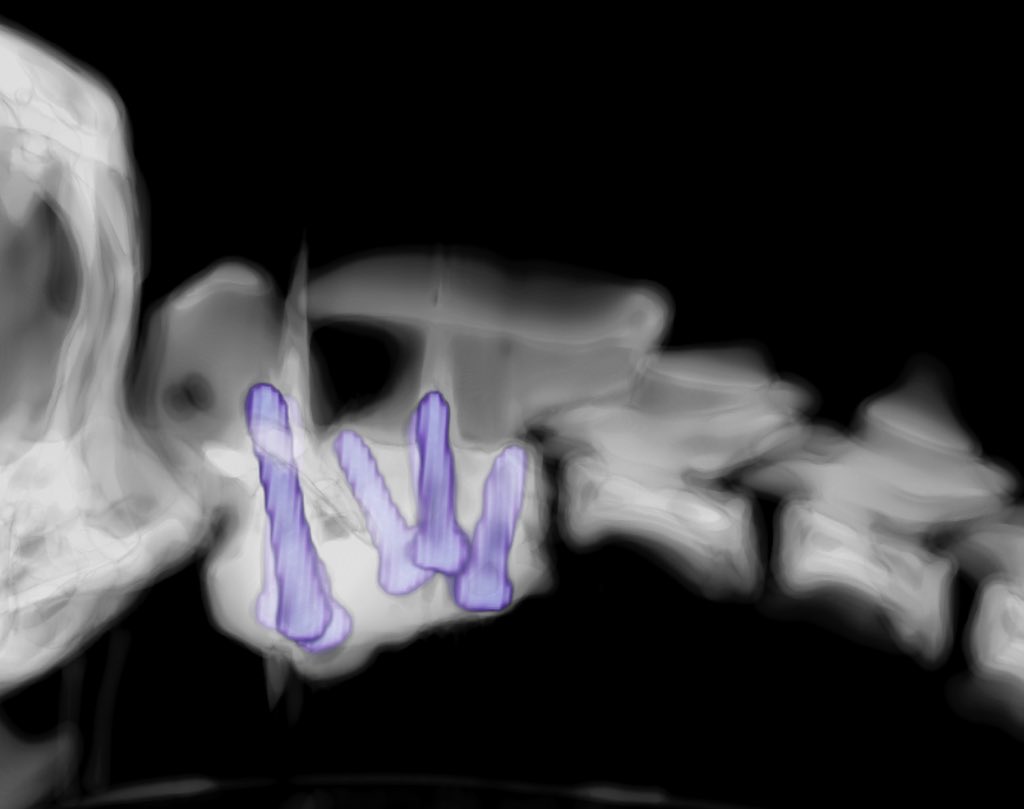

Check out this recent case from @ColinDriver1 using @FusionImplants custom 3D printed drill guides

Dr Colin Driver@neurology_vet

Lumbosacral distraction-stabilisation in Pug dog with transitional vertebral anomalies and bilateral L7 neuro foraminal stenosis. I will admit, it would be hard to hit these pedicles with big screws so perfectly without patient-specific drill guides.1/2